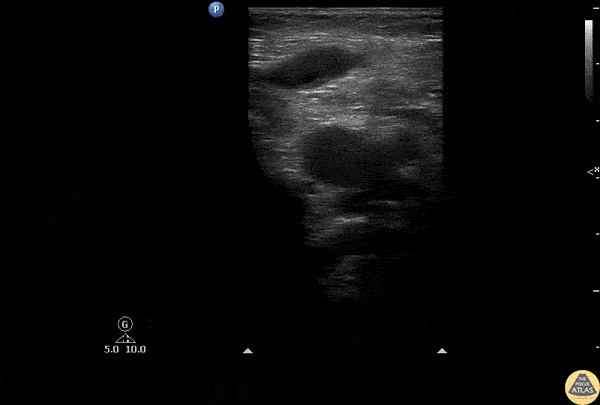

Vascular - Great Saphenous Thrombosis

POCUS of a patient with unilateral leg swelling and redness revealed thrombosis of the great saphenous vein seen as an isoechoic structure within the lumen. No DVT was noted in this patient. Image courtesy of Robert Jones DO, FACEP @RJonesSonoEM Director, Emergency Ultrasound; MetroHealth Medical Center; Professor, Case Western Reserve Medical School, Cleveland, OH View his original post here